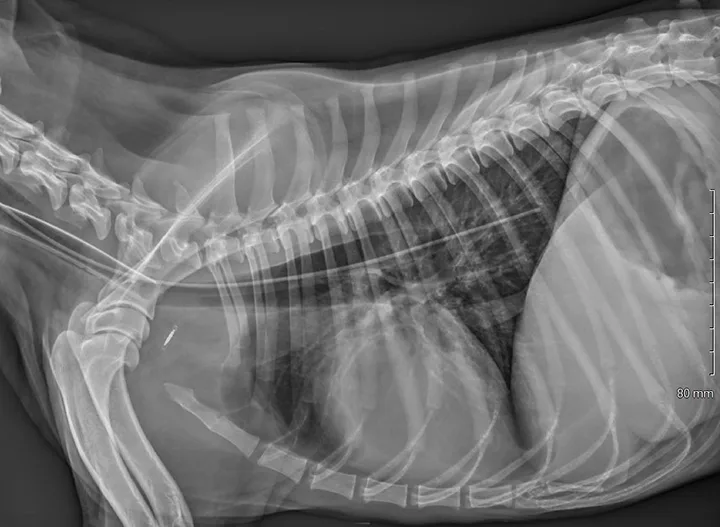

Lateral thoracic x-ray of a dog with a radiopaque feeding tube seen within the esophagus.

Radiograph of a dog with an esophageal feeding tube placed in the distal third of the esophagus